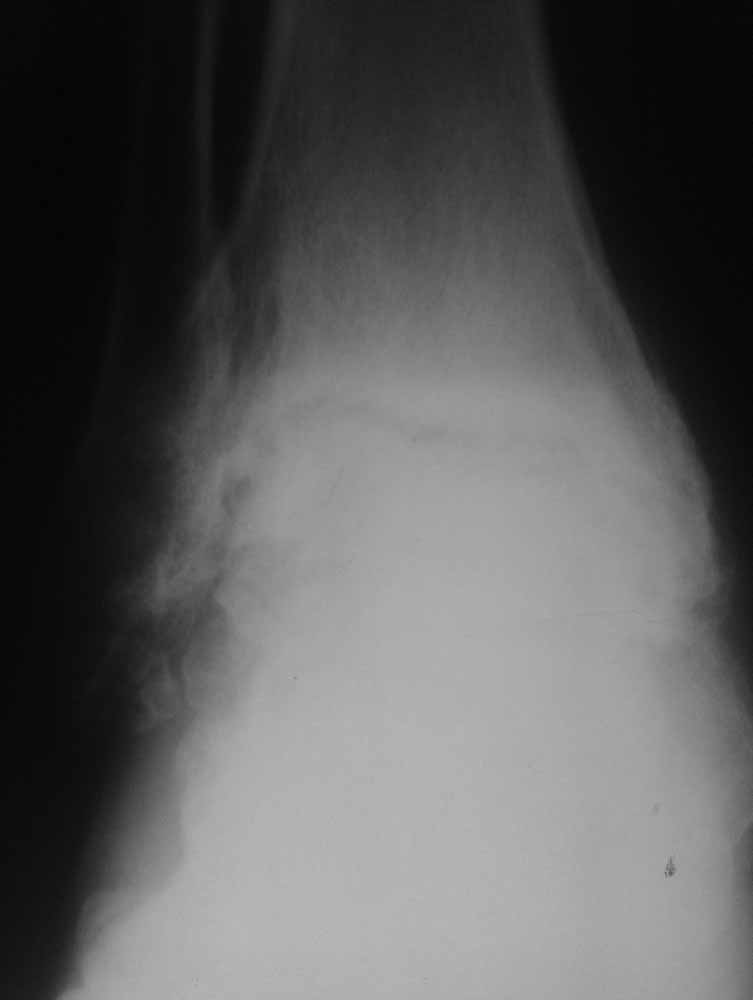

Re: Дефартроз голеностопа+перелом пилона+перелом тарана?

Жалобы со стороны второго сустава есть - прыгать на костылях до томографа без опоры на левую стопу пациенту было больно.

Зачем вытяжение - эффект на рентгенограммах виден.

Склоняемся к мысли, что все таки Charcot's Joint.

Планируем артродез стержнем правого голеностопа + аппарат на левый голеностоп.

Остается вопрос - как монтировать ? одномоментно корректировать или все таки постепенно аппаратом?